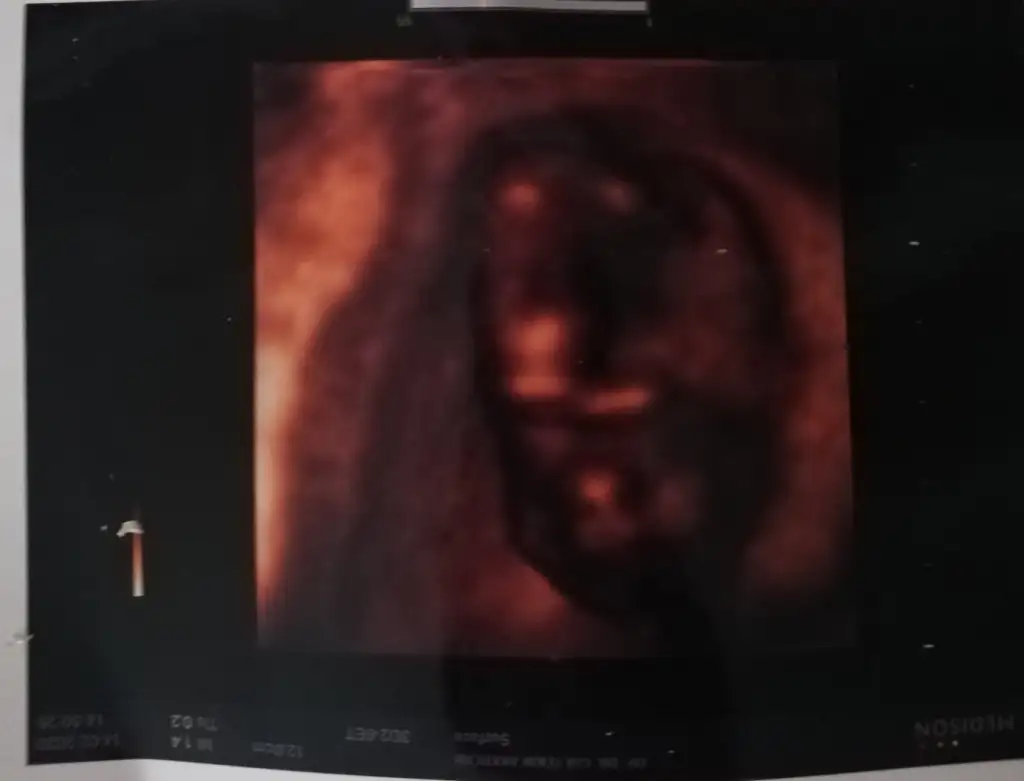

Kızlar sizce bebişimin cinsiyeti nedir?

Canım 14+2 doktorum kıza benzetti dedim ben tereddutteyım daha önce erkeğe benzetildi ikili yltarama testinde İkra meyra

Dr. umda çok düşük ihtimal ile kız olabilir diye tahmin etti. Ama netlik için çok çok erken 2 hafta sonra netleşir dedi.